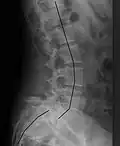

| X-ray of the lateral lumbar spine with a grade III anterolisthesis at the L5-S1 level | |

X-ray of a grade 4 anterolisthesis at L5-S1 with spinal misalignment indicated